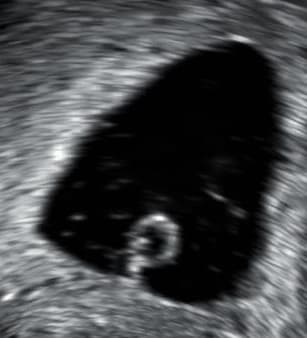

La fausse couche, ou avortement spontané, est l'interruption précoce de la gestation, qu'elle soit spontanée ou provoquée par une cause soit pathologique, soit traumatique. On la distingue de l'accouchement prématuré relativement à l'absence de viabilité du fœtus (mort-nés compris). Elle se solde par l'expulsion par voie basse de cette progéniture non-viable hors de la matrice utérine. Les fausses couches spontanées peuvent être primaires (sans enfant vivant déjà né) ou secondaires (avec enfant vivant déjà né). Elles sont précoces si la mort embryonnaire intervient avant la douzième semaine d'aménorrhée (cas de loin le plus fréquent), au-delà on parle de fausses couches spontanées tardives. Le diagnostic de fausse couche doit porter sur : preuve biologique, échographique ou anatomopathologique. Environ une grossesse sur quatre se solde par une fausse couche et une femme sur trois environ fera une fausse couche dans sa vie. Le risque augmente avec l'âge et peut atteindre 50 % ; il est également plus élevé quand la grossesse n'est pas connue. La première cause de fausse couche est une anomalie chromosomique. La fausse couche est accompagnée de saignements qui peuvent être importants, et doit faire l'objet d'un examen médical, afin de vérifier la bonne expulsion du placenta, l'absence d'hémorragie, la nécessité d'un traitement en cas de rhésus négatif. Après une fausse couche, du repos est nécessaire, ainsi qu'une bonne hydratation et un apport suffisant en minéraux (fer notamment) et vitamines. Un accompagnement médical ou psychologique peut être nécessaire. Une fausse couche aurait tendance à favoriser le bon déroulement de la grossesse suivante, si celle-ci a lieu dans les 6 mois qui suivent et en l'absence de risque infectieux, mais à augmenter le risque d'une autre fausse couche, au-delà. Il existe également des cas de fausses couches spontanées à répétition. On parle de maladie abortive (ou fausses couches spontanées à répétitions) après trois accidents spontanés successifs chez la même femme même en l'absence de changement de procréateur.